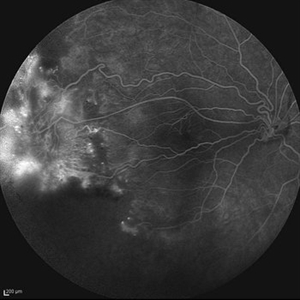

Behcet's Disease Behcet's DiseaseMar 13 2013 by Hamid Ahmadieh, MD Early phase FA of the right eye of a 23-year-old man with retinal vasculitis and branch retinal vein occlusion (BRVO) due to Behcet's disease . Photographer: Solmaz Shahmohammad, Negah Eye Center, Tehran Imaging device: Heidelberg Spectralis Condition/keywords: branch retinal vein occlusion (BRVO), retinal vasculitis